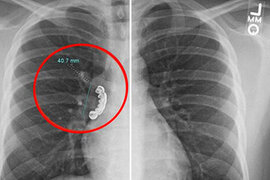

22 yaşlı gəncin protez dişi ağ ciyərinə batdı - FOTO

Amerika Birləşmiş Ştatlarında 22 yaşlı gəncin taxma dişi ciyərinə batıb. xarici KİV-ə istinadən xəbər verir ki, Uiskonsin əyalətində yaşayan gənc epilepsiya (beyindəki neyronların anidən və nəzarətsiz şəkildə boşalması) keçirən zaman gümüşdən olan pratezini udub. Bundan sonra o, şiddətli öskürək və ciyərlərind